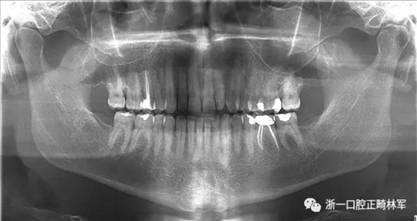

在最初的正畸咨詢期間,拍攝了口內(nèi)和口外照片連同一張全景片(圖2),一張側(cè)位頭影片(圖3)和正畸研究模型的海藻酸鹽印模。

用最大的金屬托盤來印模(尺寸 6 X-Large Upper[navy] and Lower [navy] 永久鎖不銹鋼印模托盤; ASA DENTAL,Jericho, NY),但下頜托盤不夠伸展,也就是不能很好地適應(yīng)患者口腔的解剖結(jié)構(gòu); 此外,進(jìn)行印模的助手身體健壯,在操作過程中施加了過大的壓力,導(dǎo)致了患者下頜舌骨嵴區(qū)域的疼痛。

兩天后,患者自述覆蓋在下頜舌骨嵴的一塊粘膜脫落,暴露了下方的骨質(zhì)(圖4),伴有疼痛和燒灼感,特別是與某些食物(面包,辛辣食物)相關(guān)。 因此,他被轉(zhuǎn)診到了荷蘭阿姆斯特丹的學(xué)術(shù)醫(yī)學(xué)中心的口腔頜面外科治療舌側(cè)下頜骨骨壞死。